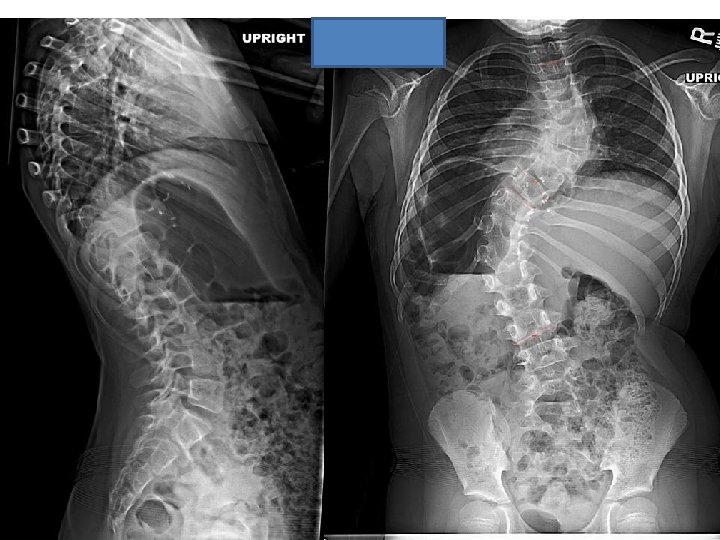

Case # 1 • M. S. is a 7 year 8 month old female with Prader-Willi syndrome. She had progressive scoliosis diagnosed at 1 year of age. She underwent MRI of the entire spinal cord demonstrating no abnormalities. She had no congenital deformities with normal spinal cord. Her neurological examination was significant for diffuse low tone with normal abdominal reflexes and absent Babinski. She began independent ambulation at 21 months of age. M. S. was treated with full time TLSO from 1 year of age until 5 years of age, then bending spinal orthosis. She had progressive scoliosis T 3 to T 9 R 61 degrees, T 9 to L 3 L 77 degrees with trunk decompensation.

• The surgical procedure consisted of posterior spinal arthrodesis from T 9 to T 12 with segmental spinal instrumentation from T 2 to L 3 in a guided growth construct. • One year post-op, the growth from T 1 to T 12 was 1. 4 cm. , and the growth from T 1 to S 1 was 3. 0 cm. based on Surgimap spine software (Nemeric, Inc. ).

Post-op

One year post-op